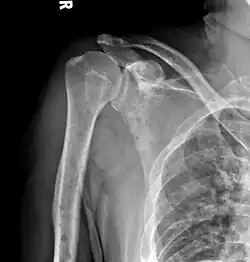

The diagnostic examination of a person with suspected multiple myeloma typically includes a skeletal survey. This is a series of X-rays of the skull, axial skeleton, and proximal long bones. Myeloma activity sometimes appears as "lytic lesions" (with local disappearance of normal bone due to resorption) or as "punched-out lesions" on the skull X-ray ("raindrop skull"). Lesions may also be sclerotic, which is seen as radiodense.[76] Overall, the radiodensity of myeloma is between −30 and 120 Hounsfield units (HU).[77] Magnetic resonance imaging is more sensitive than simple X-rays in the detection of lytic lesions. An MRI may supersede a skeletal survey, especially when vertebral disease is suspected. Occasionally, a CT scan is performed to measure the size of soft-tissue plasmacytomas. Nuclear Medicine Bone scans are typically not of any additional value in the workup of people with myeloma (no new bone formation; lytic lesions not well visualized on nuclear bone scan).

Humerus with multiple myeloma lesions -

Same humerus before, with just subtle lesions